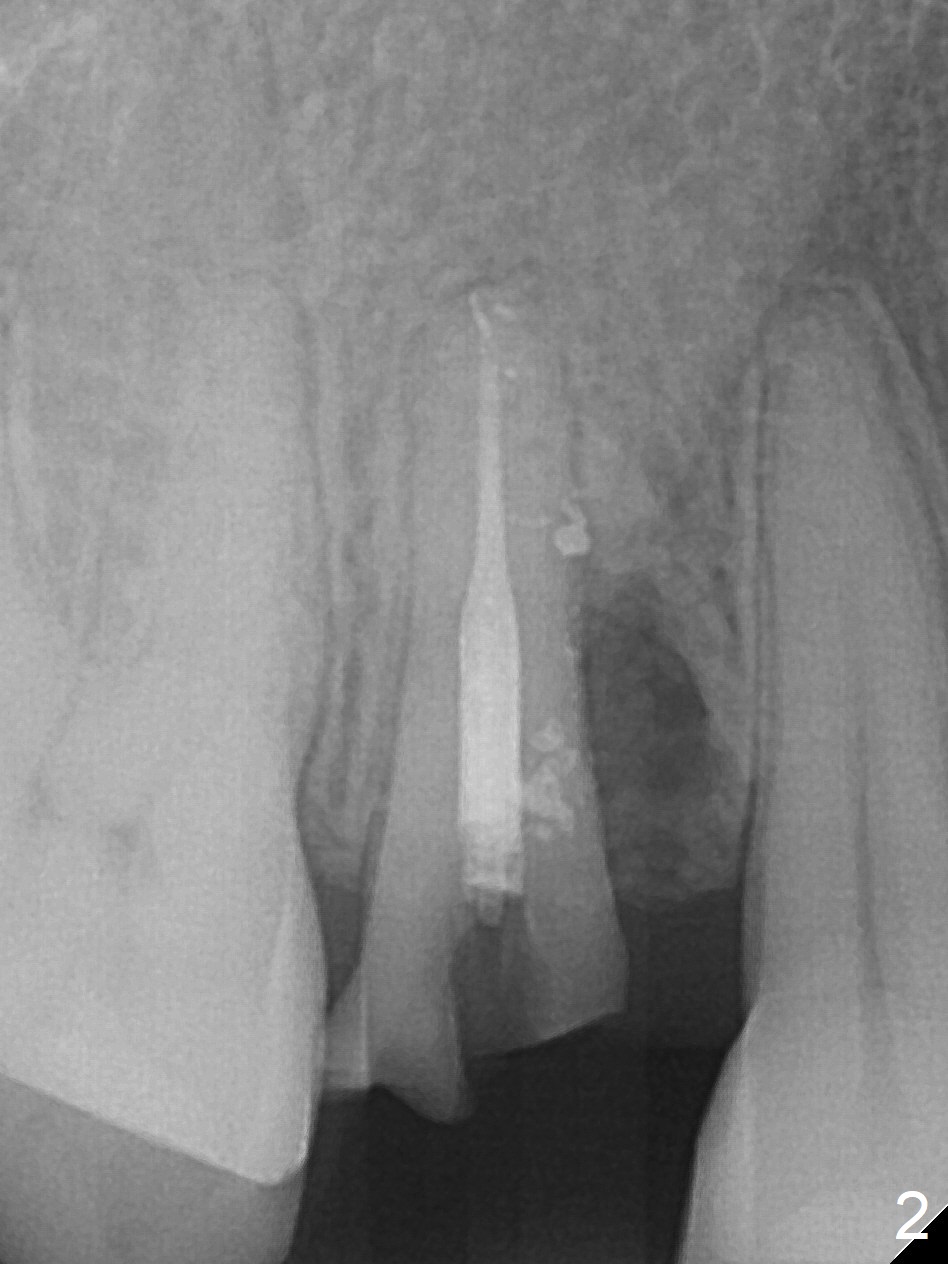

Seven years post RCT (Fig.1), the tooth #4 of a 65-year-old woman fractures subgingival palatally (Fig.2).  Since the root of the affected tooth is close to the tooth #3, osteotomy is established in the mesial slope of the socket (Fig.3).  Change the trajectory once the drill has penetrated the lamina dura of the socket (Fig.4).  The initial depth will be 20 mm for a 3.8x16 mm implant (Fig.5).